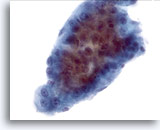

画像 4

肝FNA – 良性肝細胞

反応性変化を来した肝細胞。核は大小不同で、二核を有しています。

40倍

画像 4

肝FNA – 良性肝細胞

反応性変化を来した肝細胞。核は大小不同で、二核を有しています。

40倍